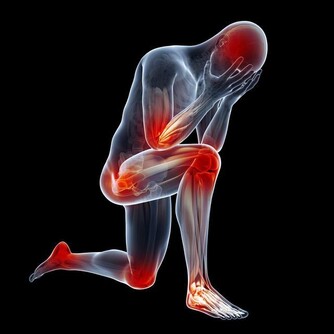

*****1“痛”>腰背痛*****

有些腰背痛,可能是腎結石的信號。

小結石,表現為絞痛,常常突然發生,感覺像刀子在割肉一般,痛感強烈;

較大的結石,常表現為腰部酸脹不適,或在運動時感到隱痛或鈍痛,痛感並不十分強烈。

有的人誤將這種痛當作腰肌勞損,導致病情惡化。提醒大家,身體出現持續的異常,一定要及時上醫院檢查,弄清原因。